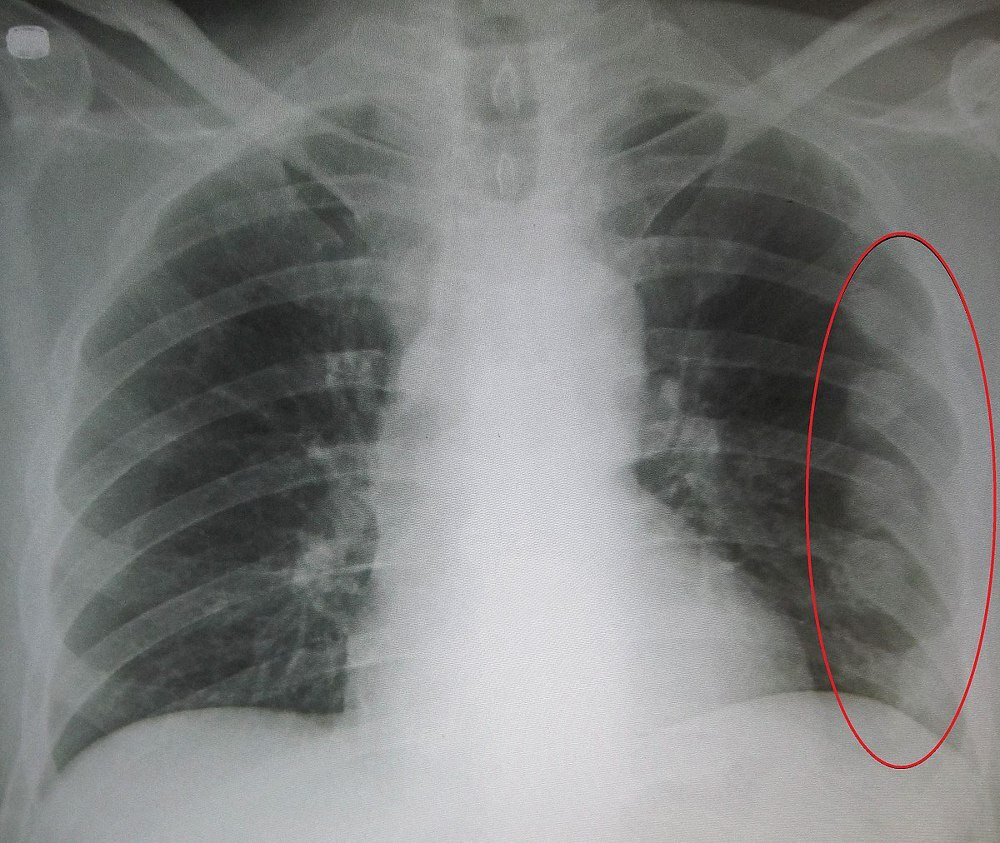

갈비뼈 금간 증상이 있다고 해서 모두 CT를 찍는 것은 아닙니다. 진료에서는 손상 경위, 통증 위치, 압통 유무, 호흡 상태, 산소포화도, 흉부 청진 등을 먼저 확인합니다. 단순 골절 의심이며 호흡 상태가 안정적이면 엑스레이 없이 보존적 치료를 시작하는 경우도 있습니다. 반면 외상이 크거나, 숨이 차거나, 폐 손상이 의심되거나, 다발성 골절 가능성이 있으면 영상검사가 더 적극적으로 진행될 수 있습니다. 즉, 검사 여부는 “뼈가 정말 금이 갔는지”만 확인하기 위한 목적보다, 위험한 합병증이 숨어 있는지를 판단하기 위해 결정되는 경우가 많습니다.